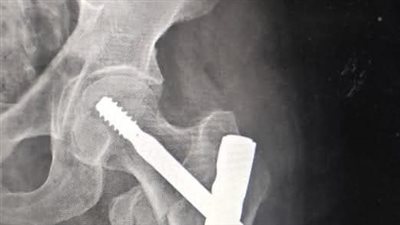

صورة ارشيفية